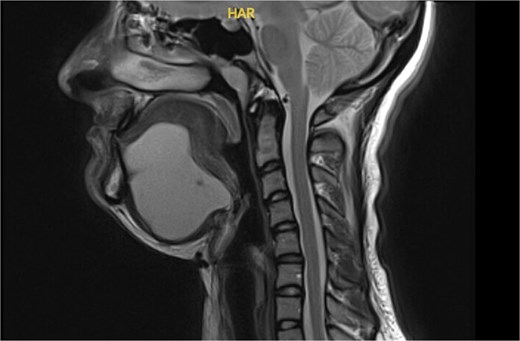

Magnetic resonance imaging (MRI) of the neck demonstrated a bilobed cystic lesion measuring 10 × 6.3 × 5.8 cm extending through the mylohyoid muscle and elevating the tongue base. The lesion displayed T2 hyperintensity consistent with a cystic structure (Fig. 3). No cervical lymphadenopathy was present. Differential diagnoses included foregut duplication cyst, dermoid cyst, and thyroglossal duct cyst.

MRI neck with contrast showing a bi-lobed cystic mass extending to tongue base.